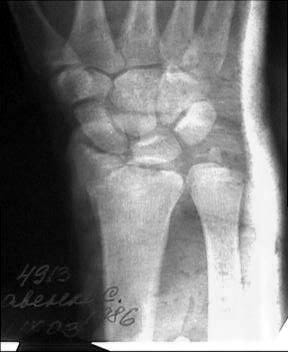

Прооперировали. Провели откытую репозицию , фиксацию спицами, иммобилизация гипсовой повязкой.

НСО г Куйбышев ЦРБ

Зырянов Сергей

Кликните для загрузки файла 28 10 03 _.jpg